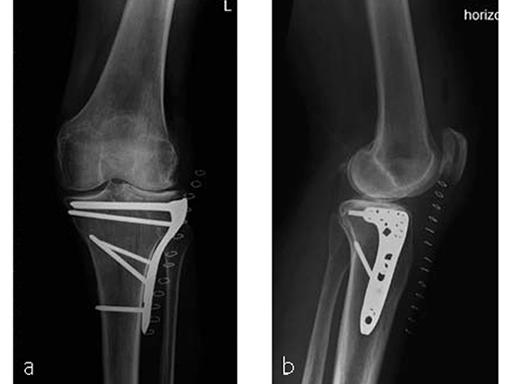

The area was functional soon after treatment (Fig 3), and the patient was able to experience weight bearing of 20 kg for the first 6 weeks. She was completely pain free after 6 weeks (Fig 4) with excellent muscular function and coordination, therefore unlimited weight bearing after the first follow-up was enabled.